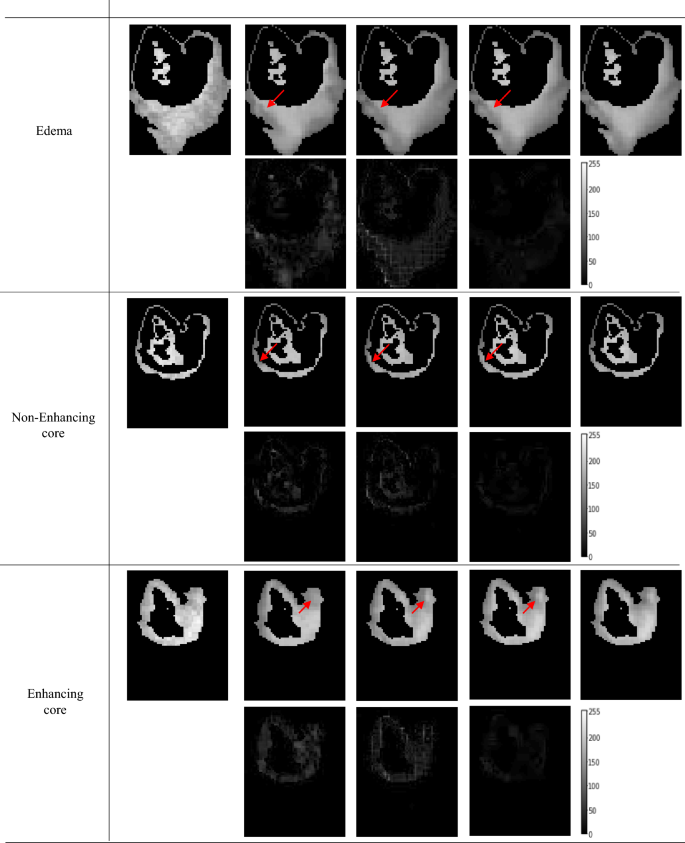

Figure 4 shows one example from the N = 500 tested subset; each one of the six panels includes the synthetic 64mT FLAIR (upper left), the inference outcomes for the three tested models (columns two to five) followed by the corresponding BraTS 3T FLAIR (the ground truth from which the synthetic 64mT was generated). In each panel the second row is the pixel-to-pixel difference between the inference outcome and the ground truth 3T. According to Fig. 4, the SR3 model consistently demonstrates better tumor enhancement across all tissue types. This is also evident in the error maps, i.e., difference enhanced minus ground truth, SR3 outperforms other models in accurately capturing the characteristics of all tumor types. Please note that the error maps are presented with increased brightness (50% increase; pixel values multiplied by 1.5) to emphasize the degree of differences. The performance of the SR3 can be appreciated, for example, in the contrast–agent enhanced potion of the tumor. As highlighted by the arrows that point to significant areas of enhancement, the border of the contrast-enhanced core is better outlined in the SR3-enhanced images. These findings on the enhancing tumor regions showcase SR3’s ability to maintain low error despite complex textures. The error maps also reveal that SR3 achieves lower errors in healthy tissue and whole-brain reconstructions as well, preserving anatomical details more precisely than UNet and CycleGAN.

Representative outcomes from a test inference on a FLAIR image from the BraTS dataset. Arrows highlight areas with significant differences for each analyzed tissue. The pixel intensity of the error maps has been increased by 50% (multiplying the pixel values by a factor of 1.5) to improve error visibility.